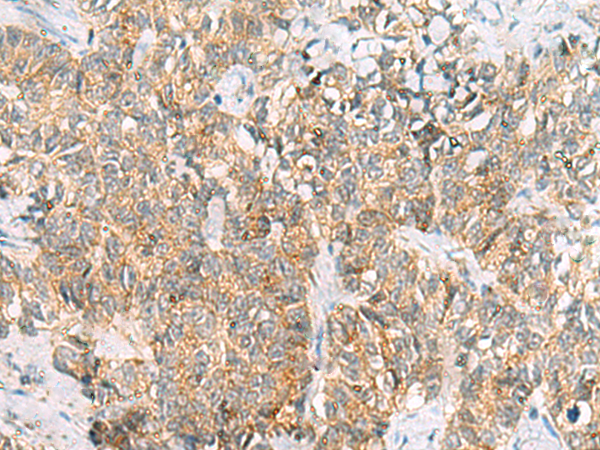

The image is immunohistochemistry of paraffin-embedded Human cervical cancer tissue using (TUFT1 Antibody) at dilution 1/120.

The image is immunohistochemistry of paraffin-embedded Human ovarian cancer tissue using (TUFT1 Antibody) at dilution 1/120.